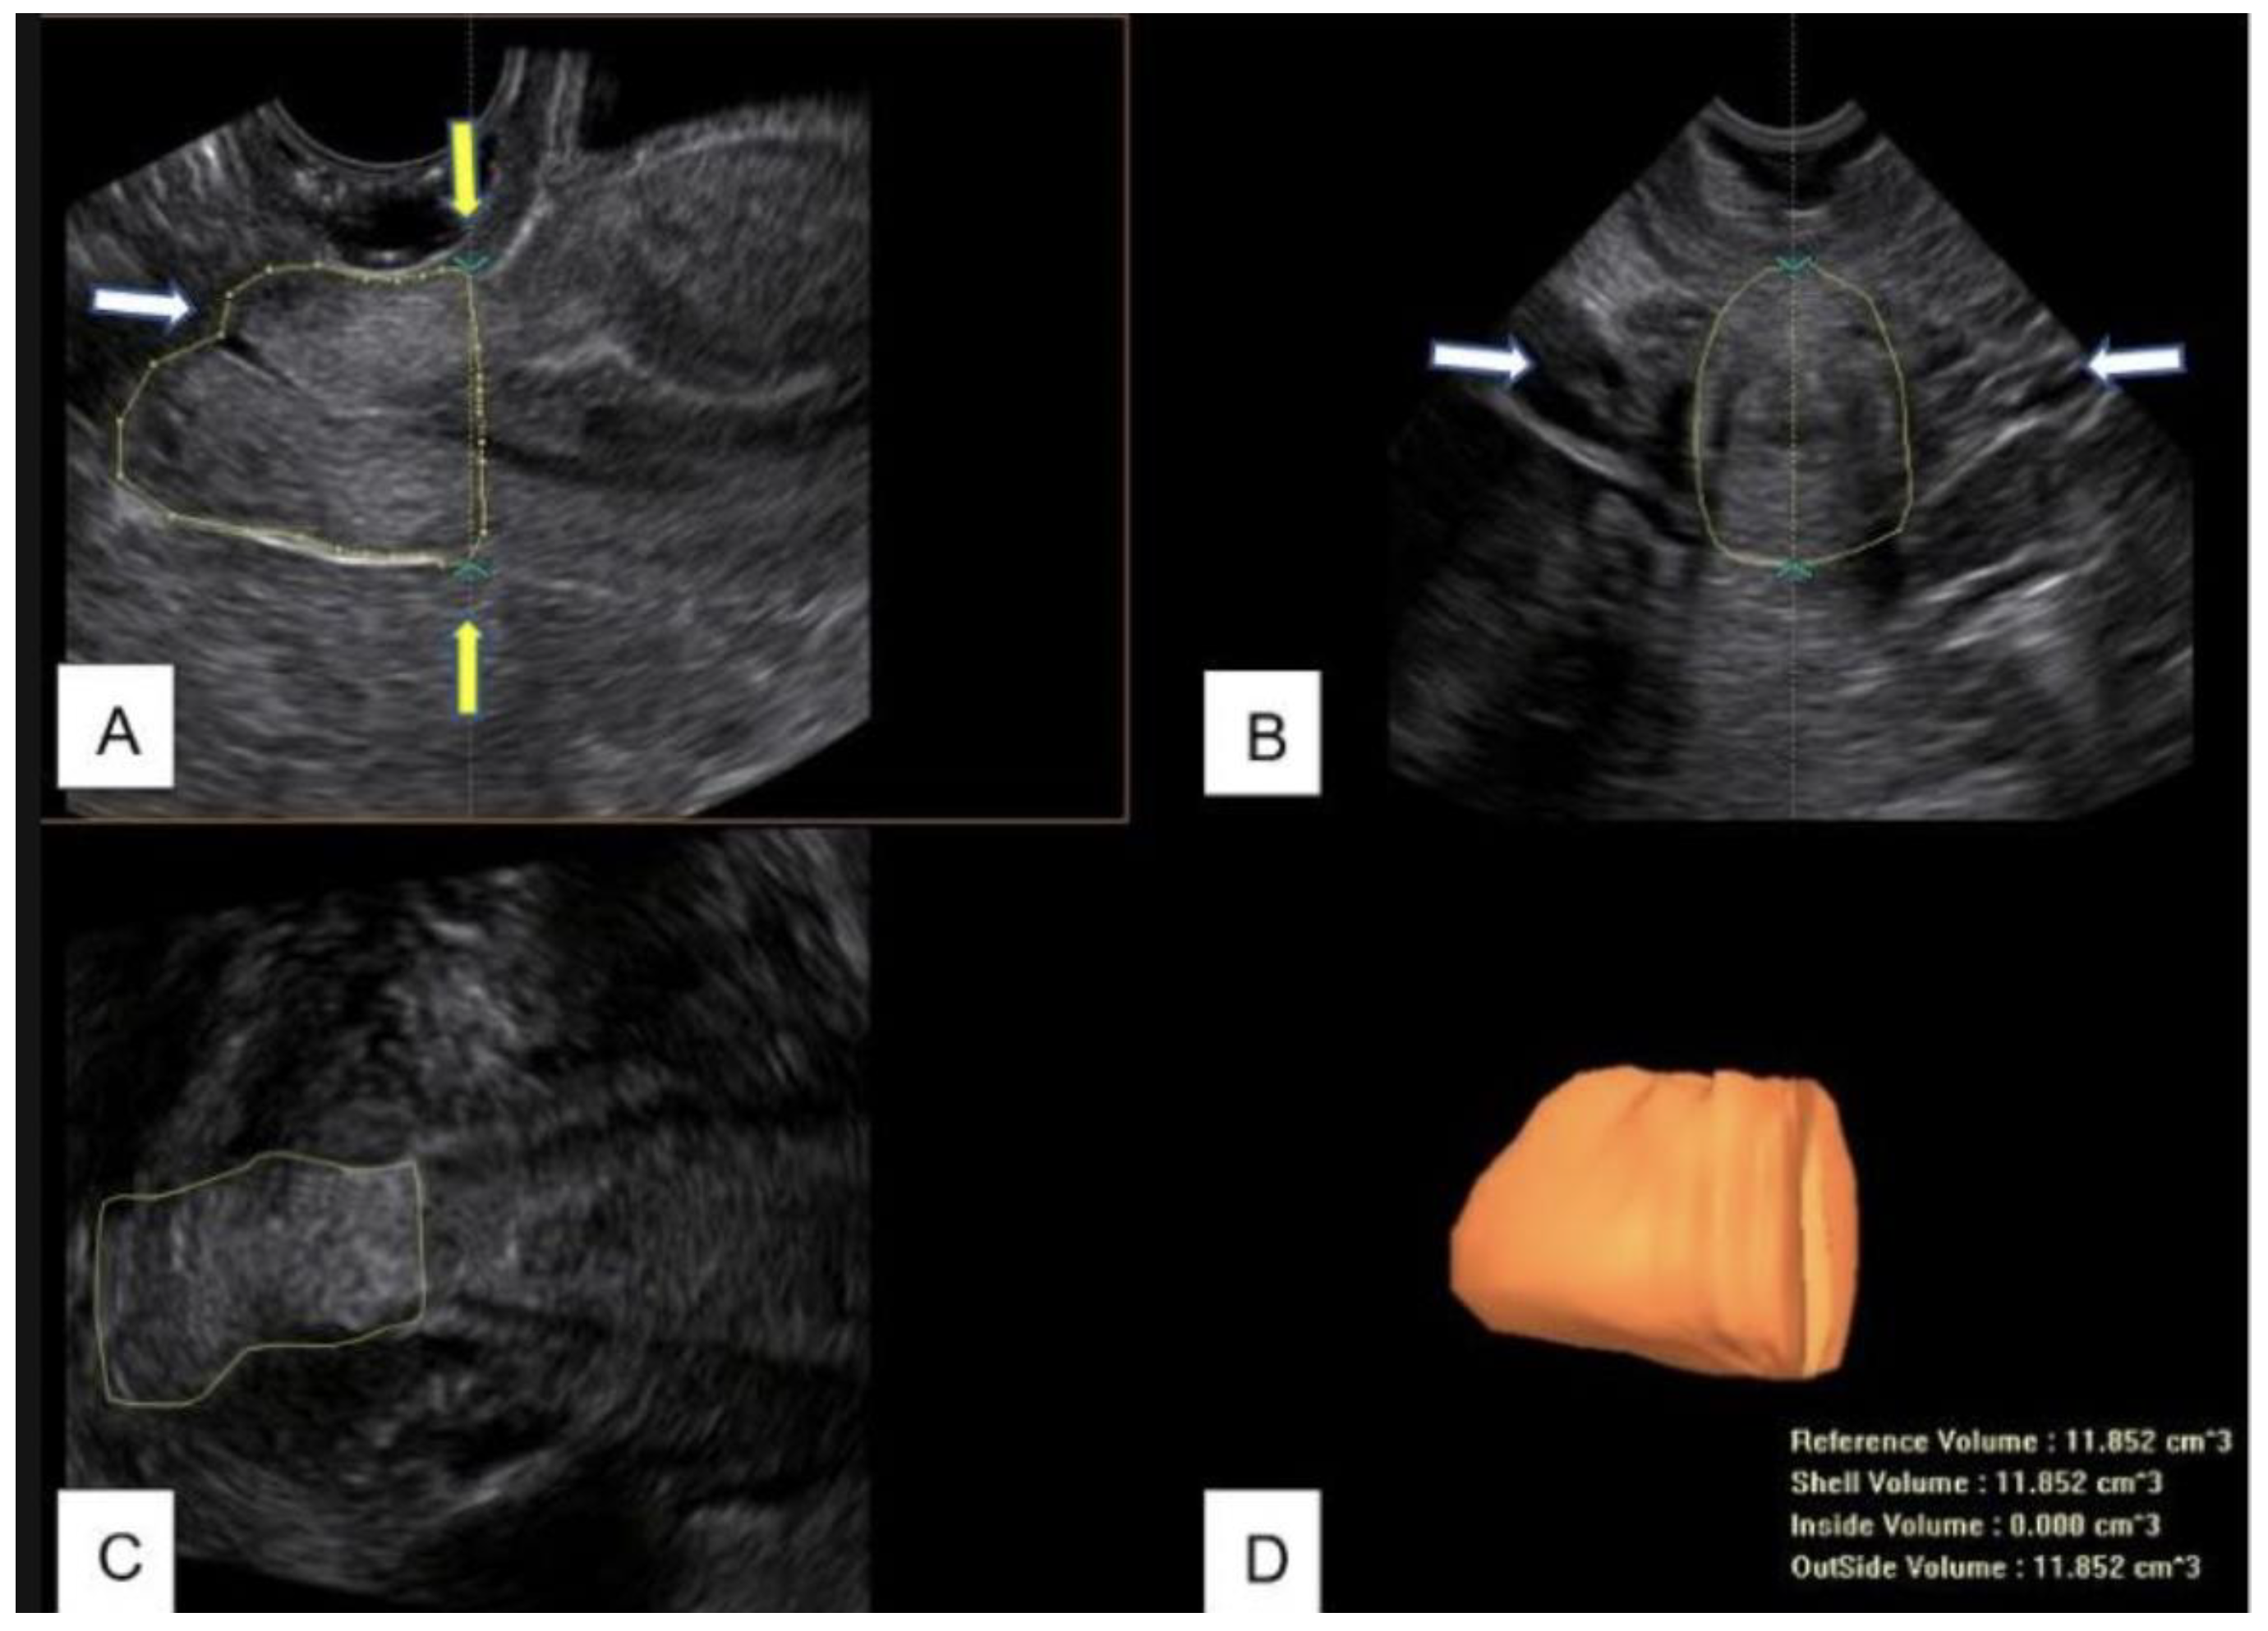

Therefore, in this study, from the acquired 3D volume, the length and the volume of the cervix were measured between this line and the external uterine os (Figure 2).

Figure 2.

(A) B-mode image of the midsagittal view of the cervix after LLETZ. The contour of the cervix is manually drawn to measure the residual volume. The white arrow indicate the uterine external os; the yellow arrows indicate the upper limit of measurement. (B) Transverse view of the cervix. The arrows indicate the uterine arteries. (C) Coronal view of the cervix. (D) Cervical residual volume obtained by Virtual Organ Computer-Aided Analysis (VOCAL™).